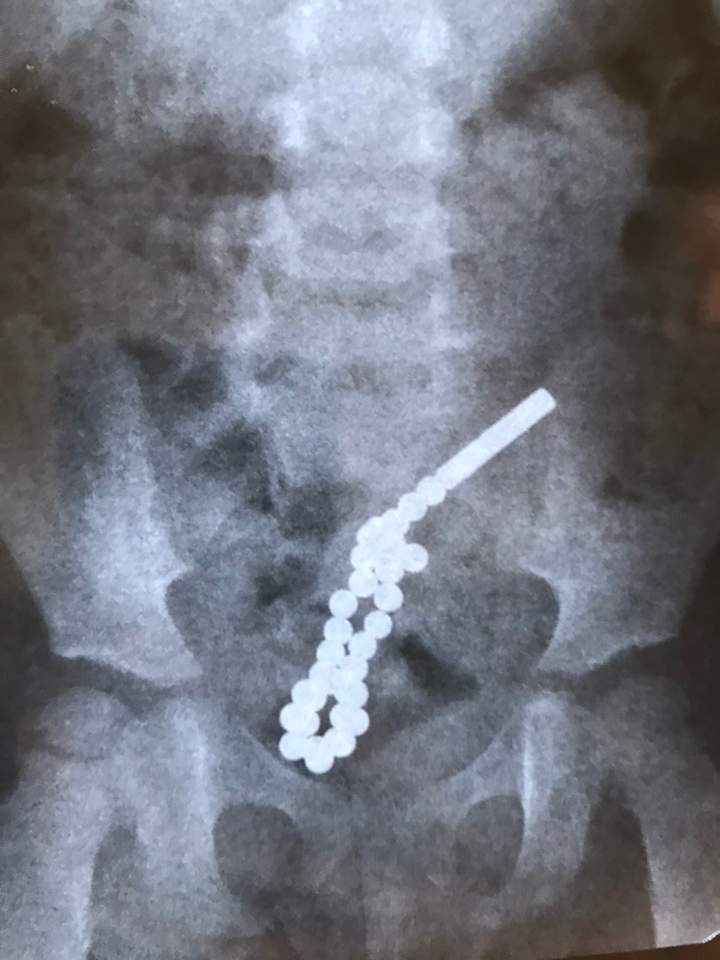

Вчора, 3 грудня, у Львівську міську дитячу лікарню потрапила дворічна львів’янка, яка проковтнула більше 31 сильно намагнічену кульку.

Ці магніти настільки потужні, що у кишківнику через стінку кишки між собою склеїлися і утворилося 7 перфоративних отворів, тобто 7 дірок.

Як повідомив дитячий хірург Дмитро Грицак, дитині 2 роки і сім місяців. Дівчинці спочатку була зроблена колоноскопія під час якої і було виявлено, що вже є перфоративний отвір з товстого кишківника у тонкий.

«Ми провели серединну лапаратомію, бо лапароскопічно цю операцію зробити було не можливо. Під час оперативного втручання було виявлено 7 перфоративних отворів між товстим і тонким кишківником. Отвори зашиті», – сказав лікар.